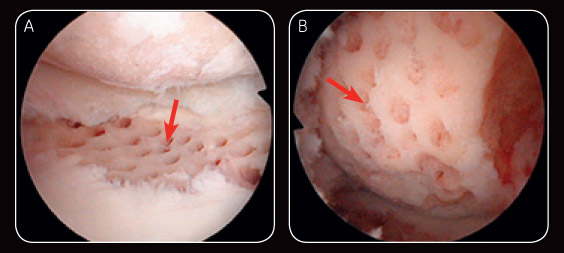

Fig. 1 Arthroscopic image illustrating post-subchondral drilling over the lateral tibial plateau (A) and post-subchondral drilling of the lateral femoral condyle (B).